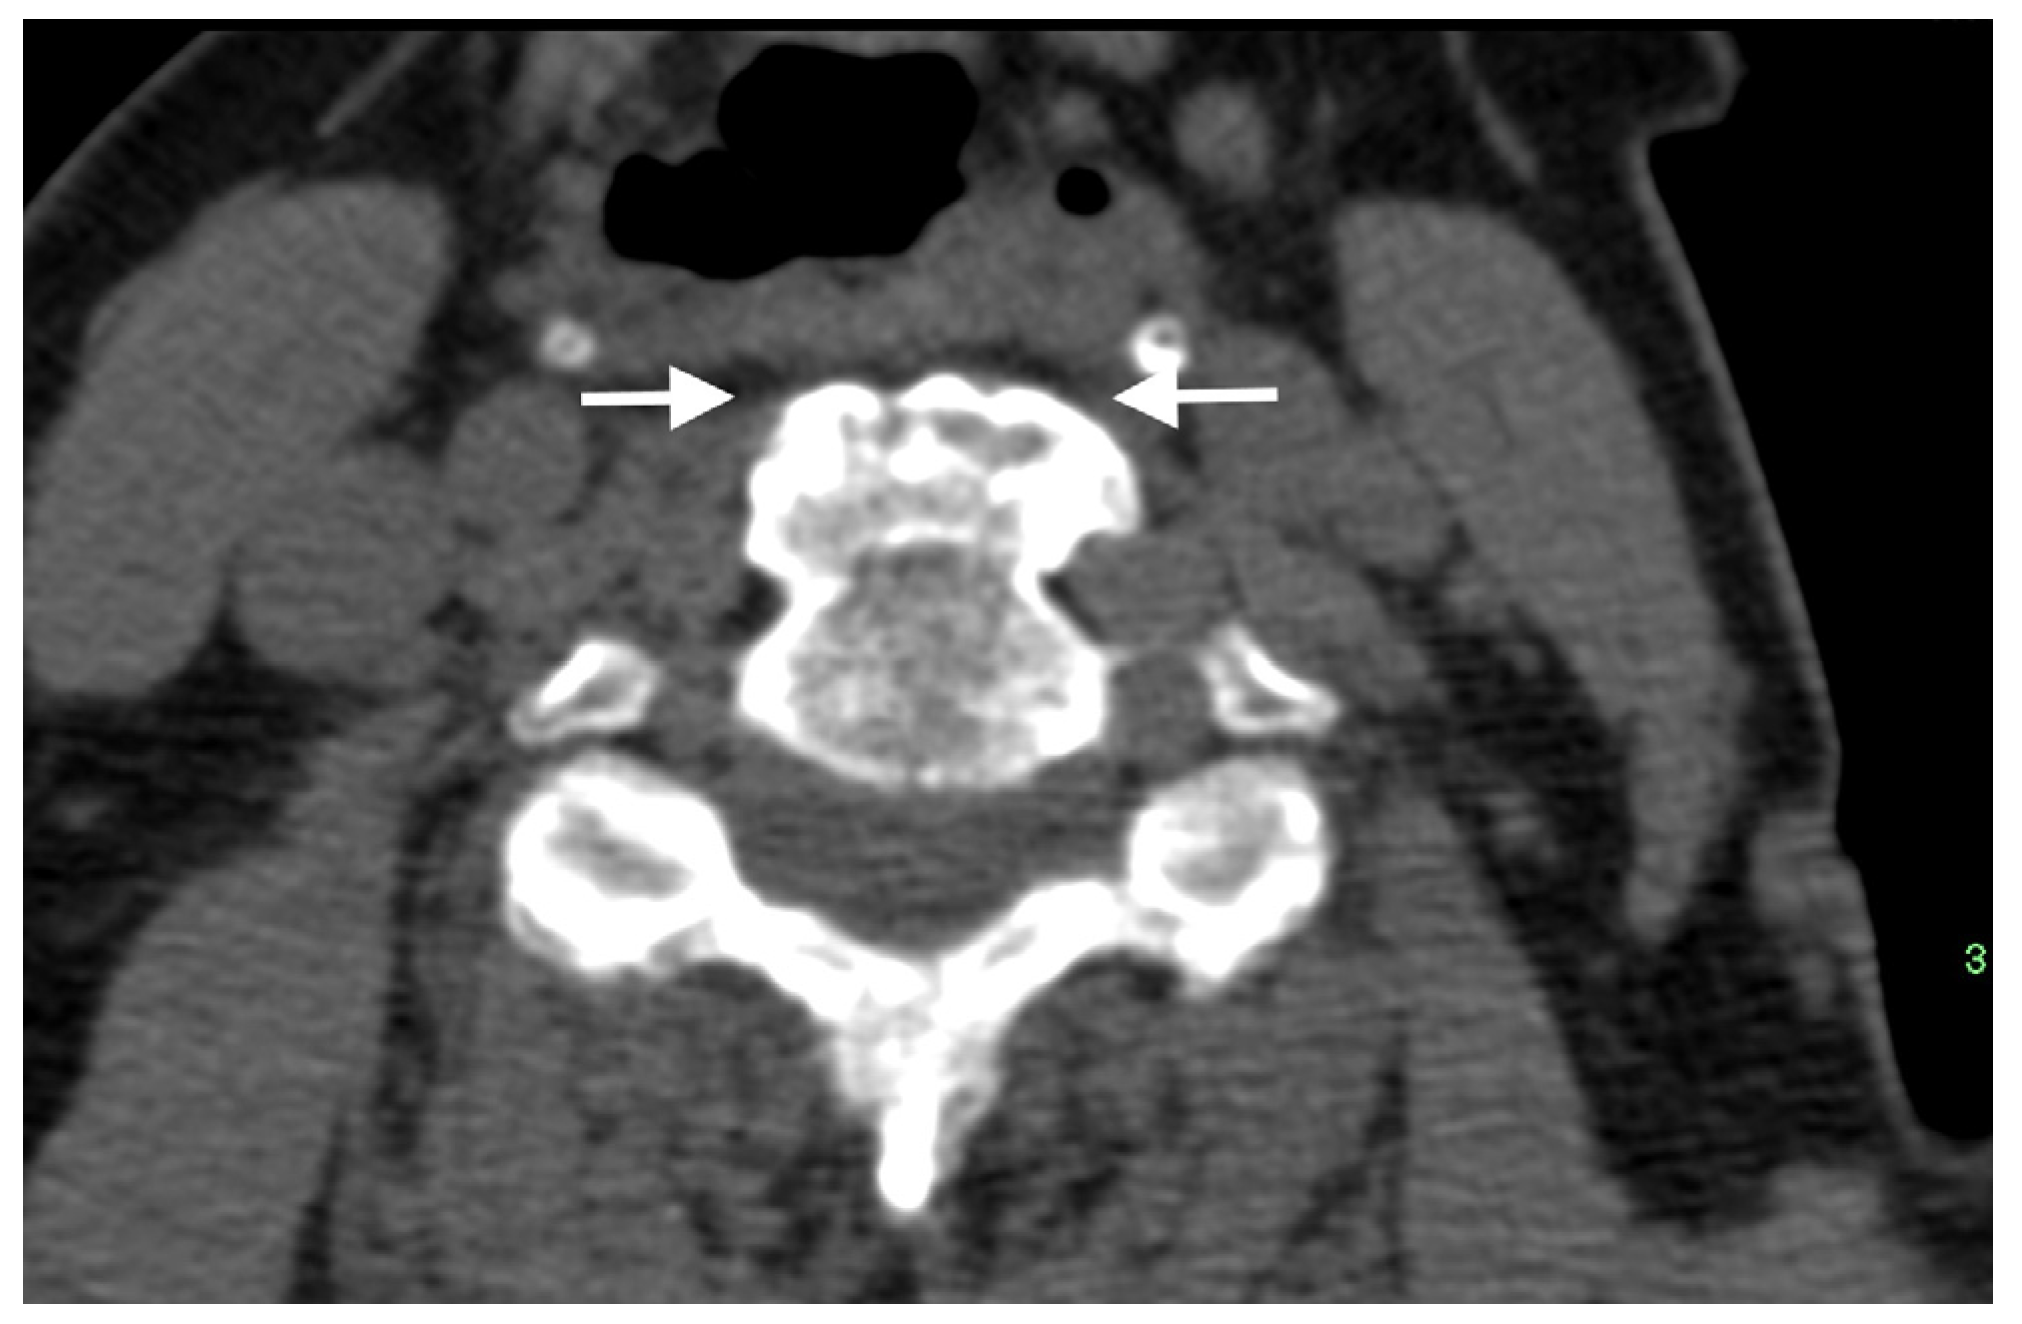

Figure 3.

Axial CT image of a thick anterior osteophyte in the cervical spine of a patient with DISH that is impinging and causing narrowing of the adjacent esophagus (arrows).